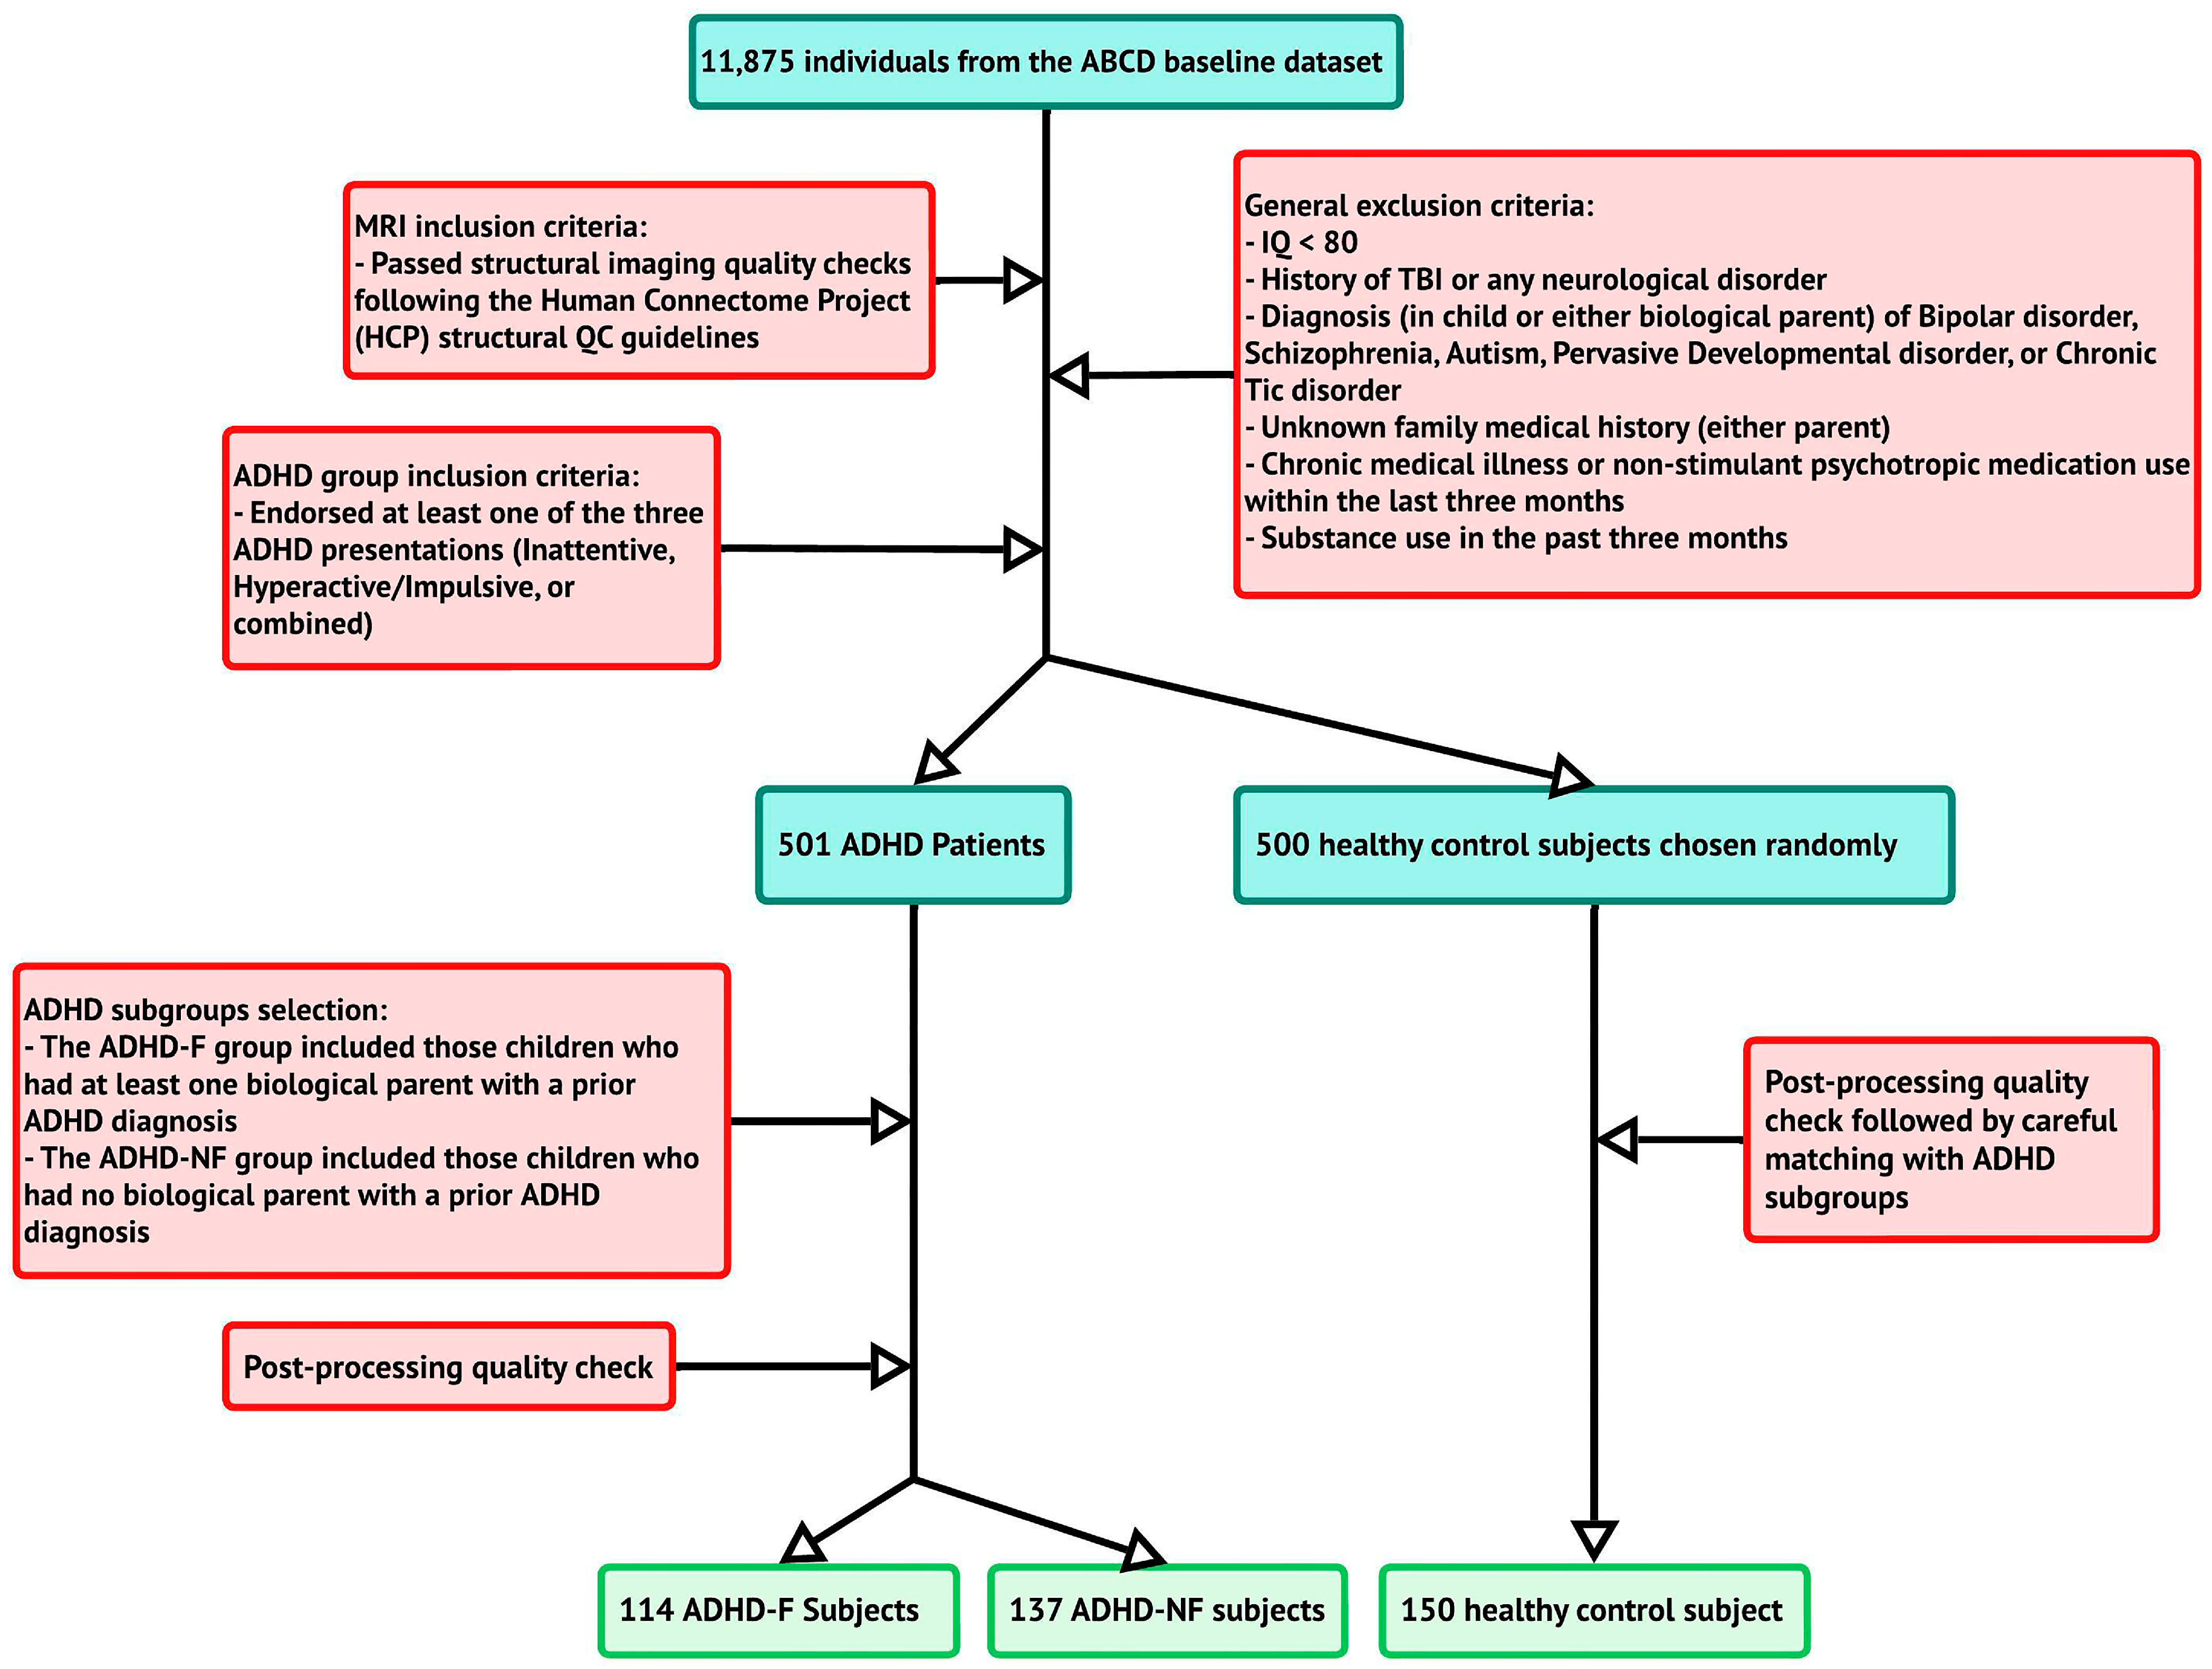

2.1. Participants